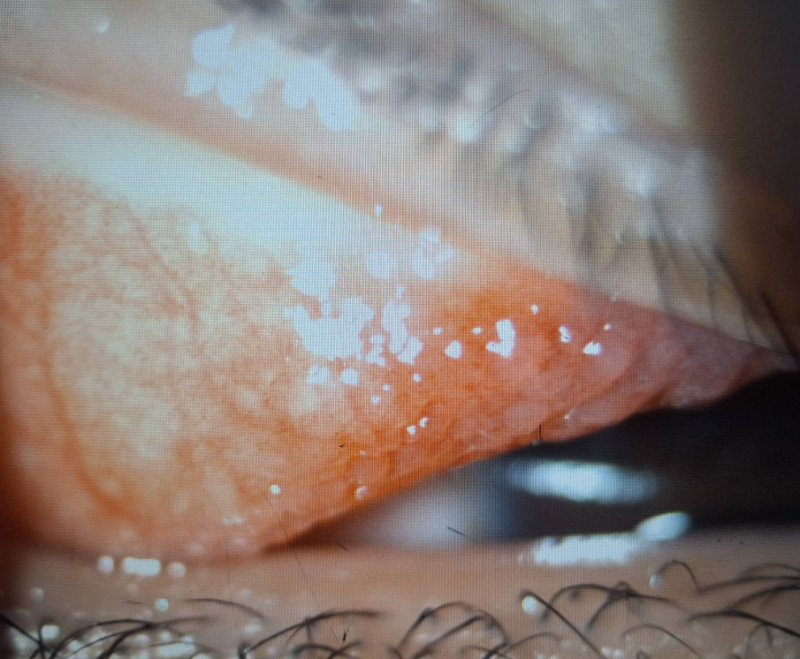

〔記者許麗娟/高雄報導〕1名國小二年級男童近半年來常覺得左眼非常癢而不斷眨眼、揉眼,近日左眼眼瞼嚴重腫脹家長帶他就醫,檢查發現上眼瞼結膜充血外,還長了許多巨大的疙瘩物,每顆直徑都大於0.1 公分,並覆蓋白色黏液,診斷為「巨大乳突結膜炎合併角膜潰瘍」,醫師提醒,孩童若不斷眨眼就應儘快就醫檢查。

達特楊眼科聯盟執行長洪啟庭指出,小二男童就醫時不僅左眼眼瞼嚴重腫脹,最佳視力僅0.5並有300度散光,應是過敏性結膜炎合併過敏性鼻炎、濕疹、異位性皮膚炎或氣喘等,因為長期揉眼導致眼皮長滿巨大乳突,因長時間壓迫造成上半部角膜有淺層潰瘍,故造成300度的高度散光和視力模糊,經強效抗生素與適當類固醇藥水治療,2星期後角膜潰瘍痊癒,乳突的也變小,學童眨眼睛的現象也明顯改善,但乳突完全消失恐要半年以上。

洪啟庭表示,台灣地區每3個學童就有1位罹患短期或長期性過敏性結膜炎,短期多是季節性過敏,長期性因慢性發炎,使結膜上皮細胞的過度增生,如本案男童長成大於0.1公分的乳突,病人會有明顯的異物感、激癢、黏液分泌物變厚、視力模糊,嚴重時還會出現角膜潰瘍。成人大多是和隱形眼鏡配戴習慣不良有密切關係,學童多為過敏反應。